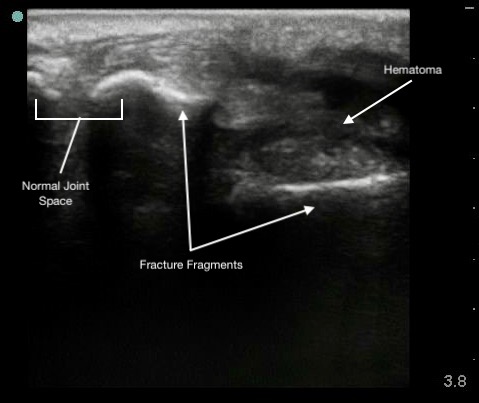

Appear as a sharp discontinuity in the bright line of the bony cortex on ultrasound.

Figure 6.

Colles (distal radius) fracture.

Hypoechoic hematoma or effusion may be visible in the surrounding soft tissue.

Ultrasound allows immediate assessment of the presence and extent of a fracture at the area of tenderness.

Capable of detecting displacement as small as 1 mm.

Less effective for evaluating fracture geometry or comminution.